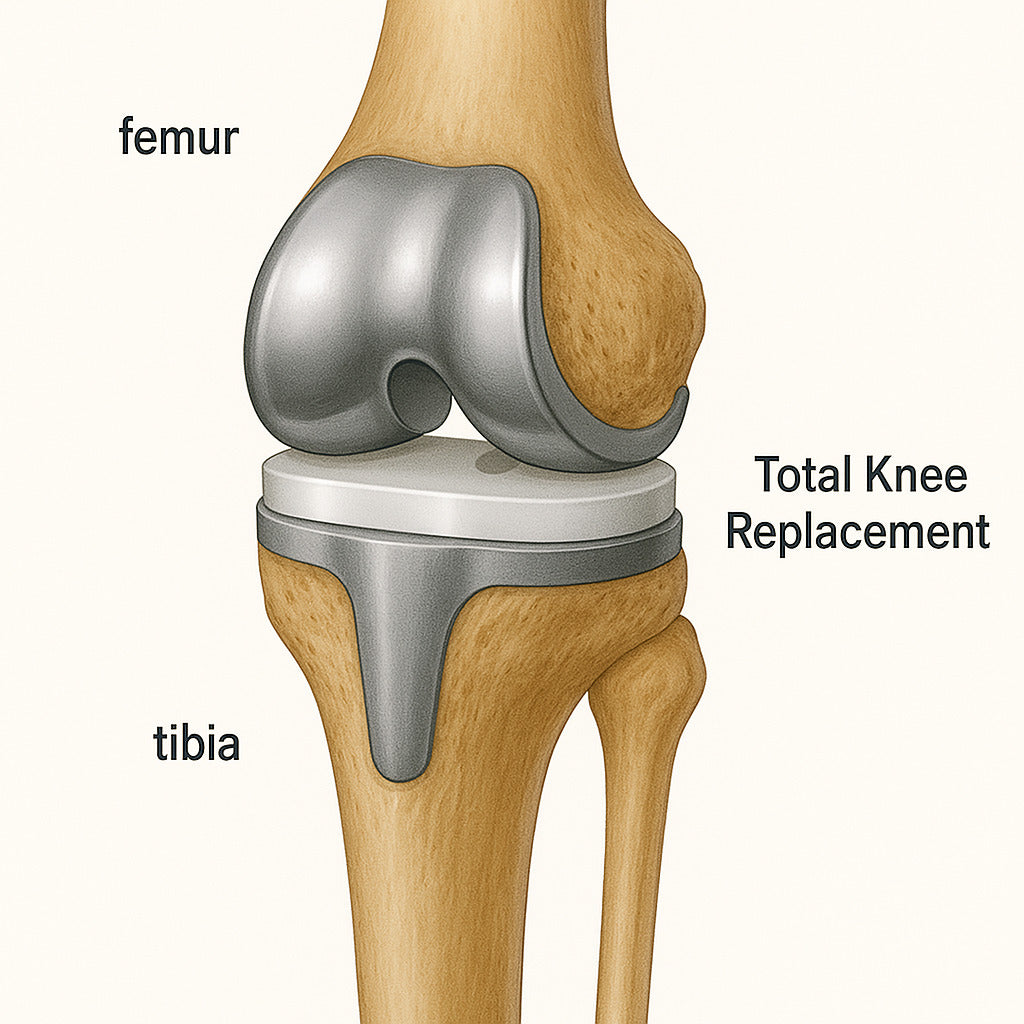

• 病人的膝關節僵硬、變形和活動能力下降,如果這非手術性的治療方法未能奏效,則可選用全膝關節置換的手術。全膝關節置換術是一種人工關節置換外科手術,是指切除機體已無法自行修復的關節面,用人工關節部件替代損壞的關節,矯正肢體力線,消除膝關節疼痛,維持關節穩定性,恢復膝關節功能的一種治療方法。